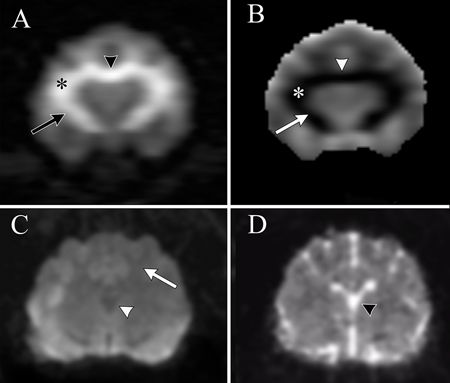

In such cases, magnetic resonance imaging (MRI) of the brain can provide valuable information regarding intoxication. T2-weighted MRI sequences can disclose marked hyperintensity of the CNS white matter as a result of edema (Figure 4). In addition, cytotoxic edema and intramyelinic edema may be observed using an MRI sequence called diffusion weighted images (DWI) and apparent diffusion coefficient (ADC) maps. White matter hyperintensity on DWI and hypointensity on ADC maps strongly support intramyelinic edema (Figure 5). Although not pathognomonic, taken together, neurologic dysfunction and MRI findings suggestive of intramyelinic edema provide strong evidence of bromethalin intoxication.

Figure 5. (A) A transverse DWI at the level of the rostral cerebrum from a cat with bromethalin intoxication. The same white matter structures--the corpus callosum (arrowhead), corona radiata (asterisk), and internal capsule (arrow)--are hyperintense (b value = 1,000 mm2/s ) secondary to edema. (B) On the corresponding ADC map, the same hyperintense white matter structures are hypointense, consistent with intramyelinic edema. (C) A transverse DWI at the level of the cerebrum and thalamus of a normal cat. Note the hypointense appearance of cerebral white matter (arrow) and cerebrospinal fluid in the third ventricle (arrowhead). (D) A corresponding ADC map shows little change in the intensity of the white matter. Note that the normal appearance of cerebrospinal fluid on the ADC map is hyperintense (arrowhead). Image courtesy of Drs. James Hammond and Jennifer Perkins.Where to measure bromethalin/desmethylbromethalin concentrations